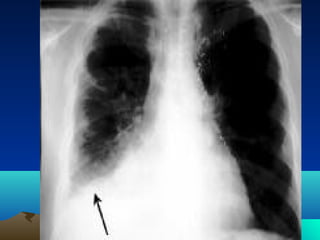

role

Only in life threatening

condition

(mass effect)